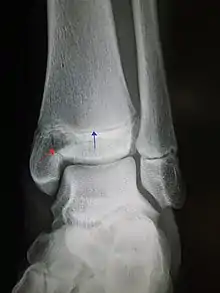

En la anatomía humana, el tobillo es la articulación donde se unen la pierna y el pie.[1] El tobillo está constituido por tres huesos: el peroné y la tibia que pertenecen a la pierna, y el astrágalo que forma parte del pie. La tibia y el peroné forman conjuntamente en su parte inferior una mortaja articular o cúpula sobre la que se encaja la troclea o polea del astrágalo.[2] El maléolo lateral va a ser más voluminoso que el medial, va a descender más y por tanto, se posterioriza más, lo que explica que exista una ligera oblicuidad (aproximadamente 20.º). Sobre la estructura ósea existe una cápsula fibrosa, un conjunto de ligamentos, músculos y tendones que contribuyen a la solidez de la articulación y hacen posible el movimiento de la misma.[3], es una articulación muy expuesta a lesiones